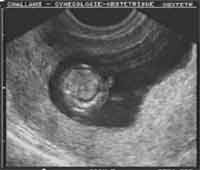

Épanchement thoracique